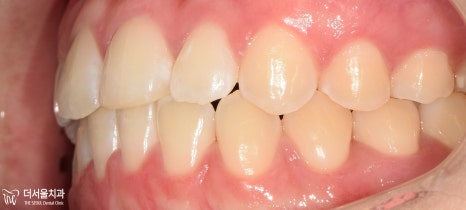

과연 구치부의 상태는 어떨까요?

교합면에서 확인해 보았더니

U자에 가까워야 될 악궁의 형태가

사각형에 가까워져 있었습니다.

하악 앞니 뻗침은 생각보다 심하네요.